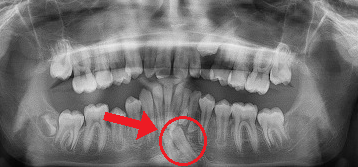

This case includes a panoramic X-ray and two segments of a CBCT (cone beam x-ray) images that highlight the importance of early screening. This patient’s permanent lower canine was unable to erupt because extra teeth were blocking its path. By identifying the problem early and removing the extra baby teeth, we were able to clear the way for the permanent tooth to come in naturally—preventing more complex treatment later.